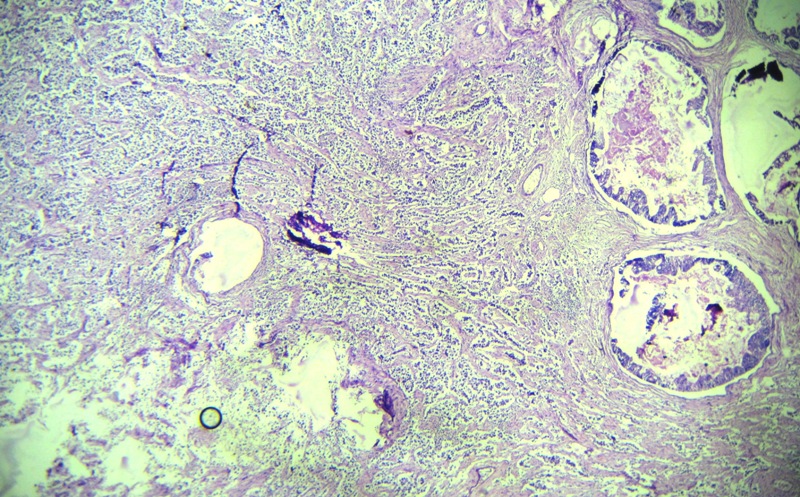

Collision tumors of ovary are rare neoplasms and most commonly consist of a teratoma with mucinous tumor. Combination of papillary serous cystadenocarcinoma and dysgerminoma was yet to be reported. A twenty years female patient presented with a large tumor of right ovary. Microscopically it was diagnosed as a collision tumor of ovary composed of dysgerminoma and serous cystadenocarcinoma. Mixed tumour can arise from divergent differentiation of a single type of stem cell. But components of collision tumor must arise from separate clones. Possibility of collision tumour should always kept in mind during assessment of difficult ovarian tumors to avoid diagnostic error.